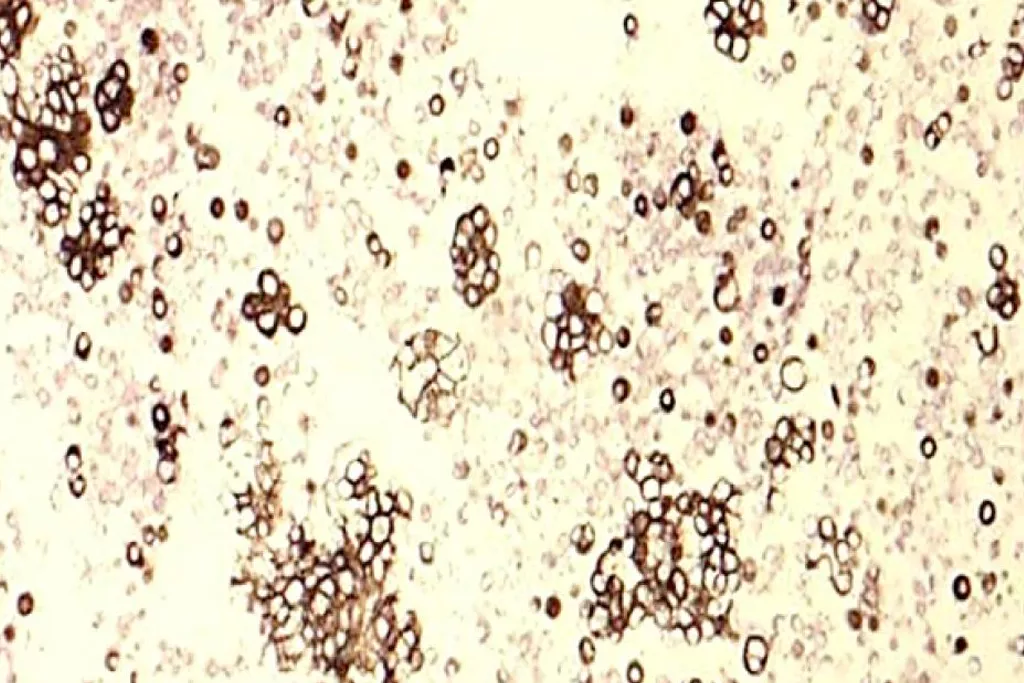

Bildgalleri2

2. Bild tillhörande Cytology Dept. Groningen University Hospital, Nederländerna